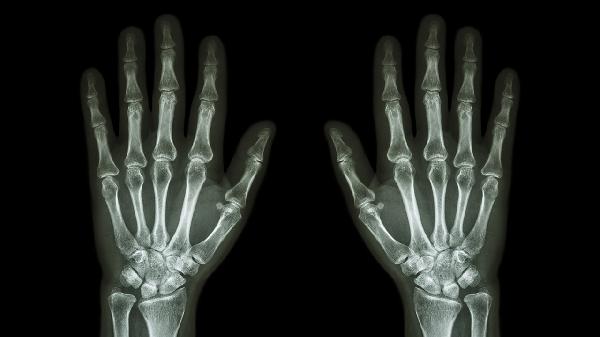

腕部骨折后如何锻炼

腕部骨折后可通过被动活动、主动活动、抗阻训练、功能性训练、器械辅助等方式锻炼。腕部骨折通常由外伤、骨质疏松、重复应力等因素引起。